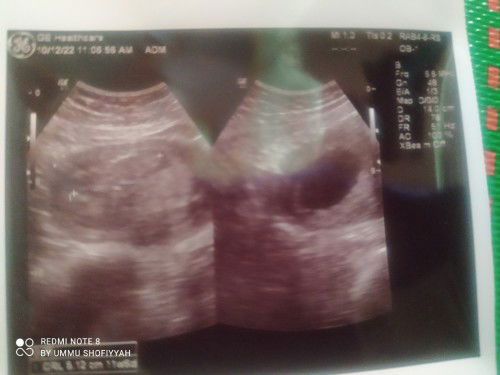

Kemarin baru selesai usg di 22 week, di vonis plasenta previa, ada sedikit plasenta yang menutup jalan lahir, posisi janin bagus kepala dibawah hanya belum masuk panggul. Adakah disini yang pernah plasenta previa 22 week setelah 7 bulan plasenta sudah ndak menutup jalan lahir lg dan udah bisa lahiran Normal? #bantusharing #seriusnanya